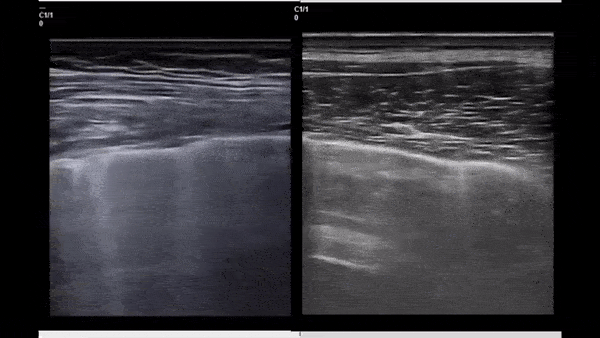

This side by side ultrasound clip compares B-lines in a patient with COVID-19 (left) and a patient with CHF (right). While subtle, the difference lies where the B-lines connect to the pleura! In COVID-19 many of the B-lines initiate from depressed/irregular areas of the pleura (imagine little holes being punched in the pleural line) while in CHF, the B-lines initiate from a smooth pleural line. These pleural defects are not specific to COVID -19 and can be seen in other viral pneumonia as well. Take Home: Not all B-lines are created equal! Image courtesy of Dr. Marco Garrone (@drmarcogarrone)